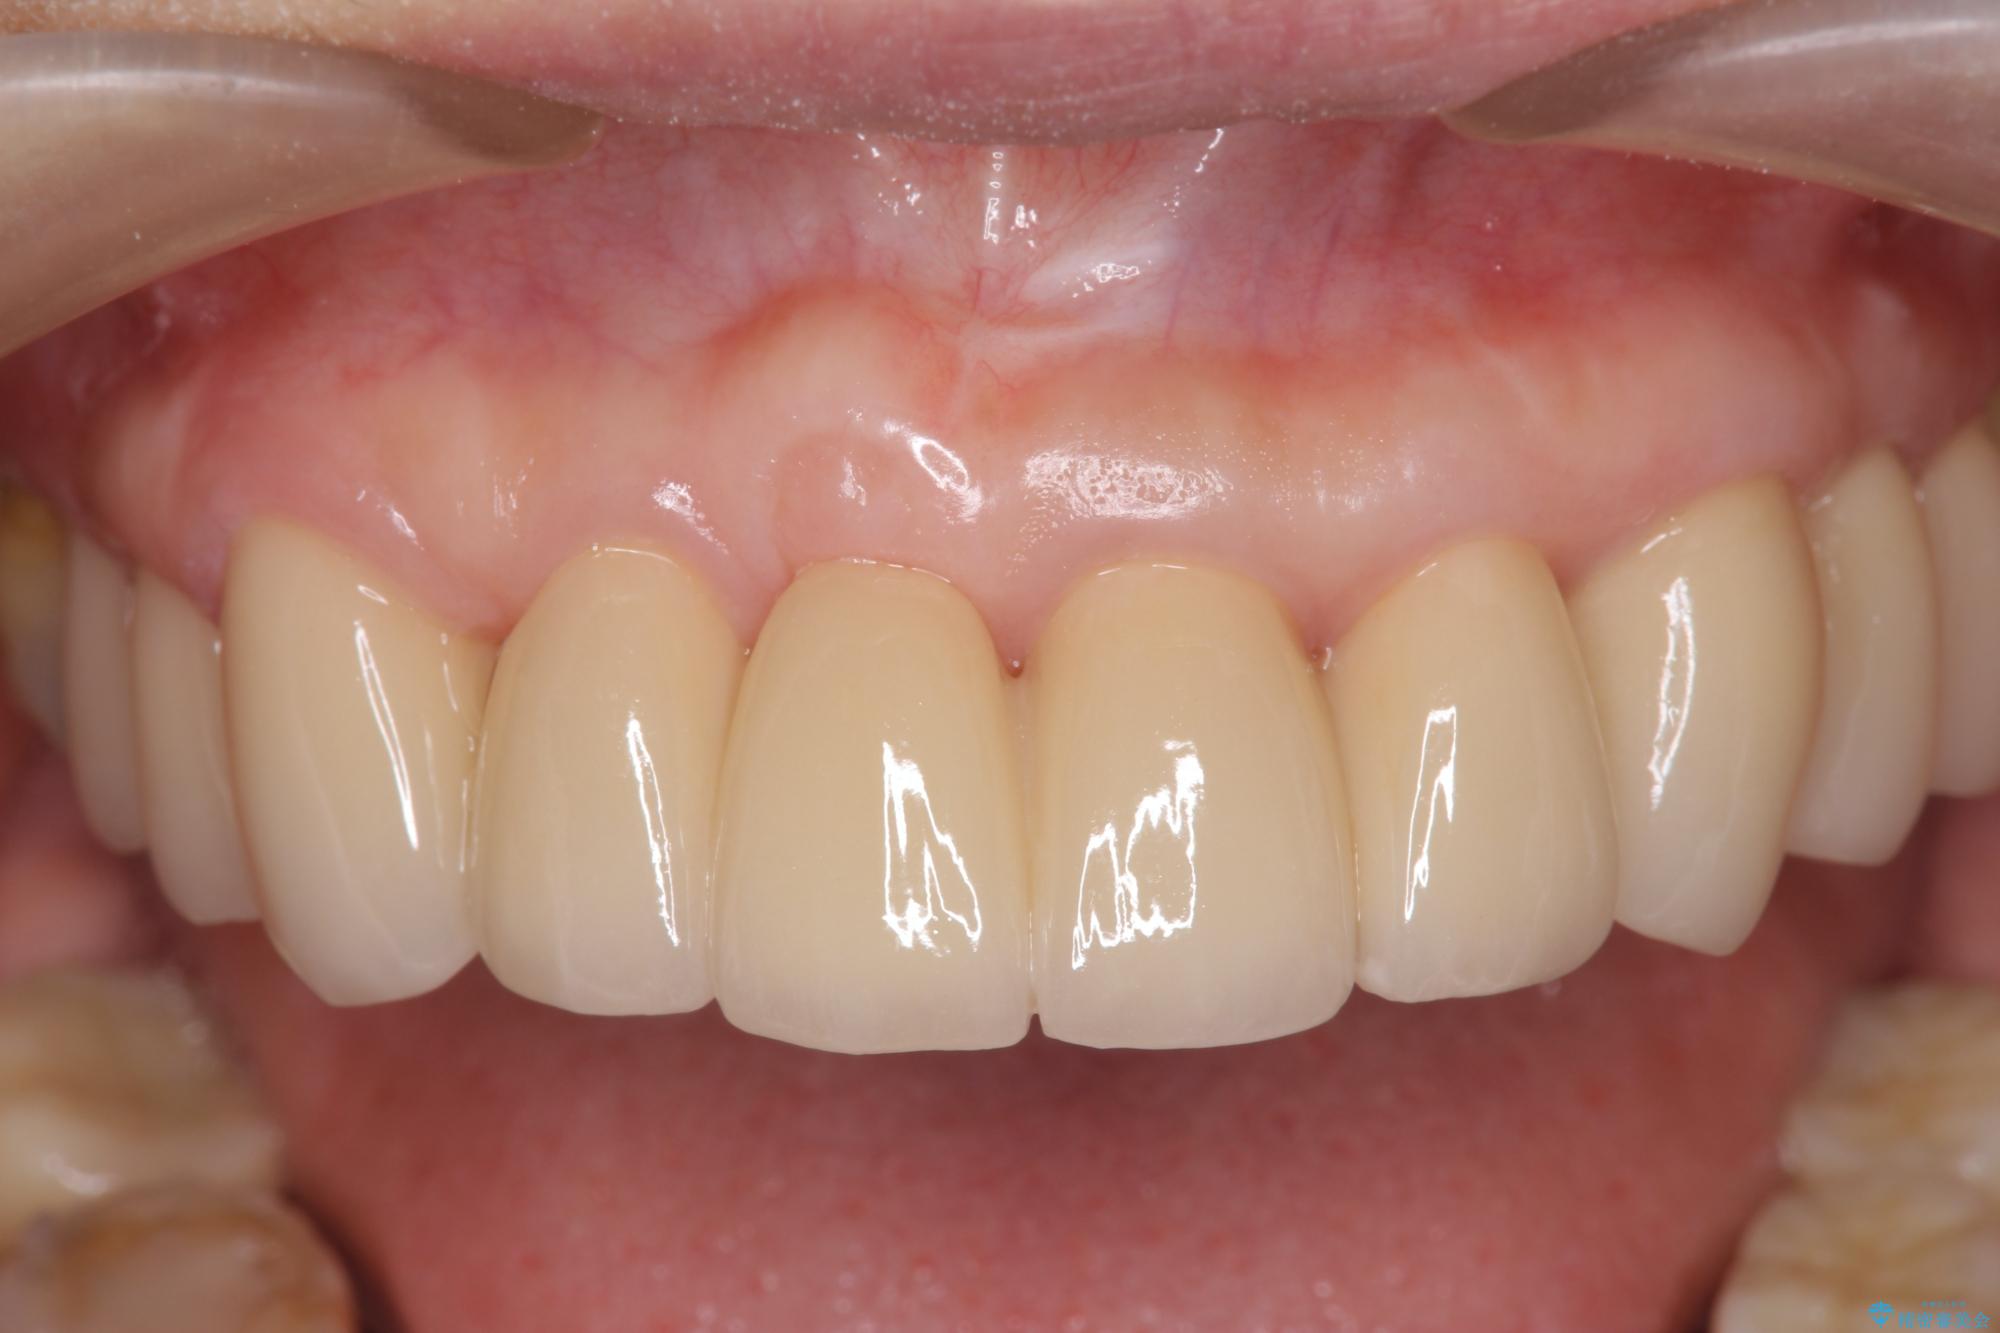

中等度歯周病の治療後にセラミックで美しい前歯に

検査の結果、歯周ポケットの測定値は4-6mm程度の値が全顎にわたって認められ、中等度歯周病の状態です。

歯を今後残し、歯周病の状態を改善するため、歯槽骨の再生治療をおこなったのち、歯周ポケットの除去、セラミックブリッジの製作を行う治療計画を実行していきます。

治療後について

歯周病によって失われた歯を支える骨(歯槽骨)に対し、再生療法を用いることで骨の再生・回復を実現しました。骨の高さが改善されたことで、歯の土台が強化され、将来にわたって歯をしっかりと支え続けられる口腔内環境を整えることができました。